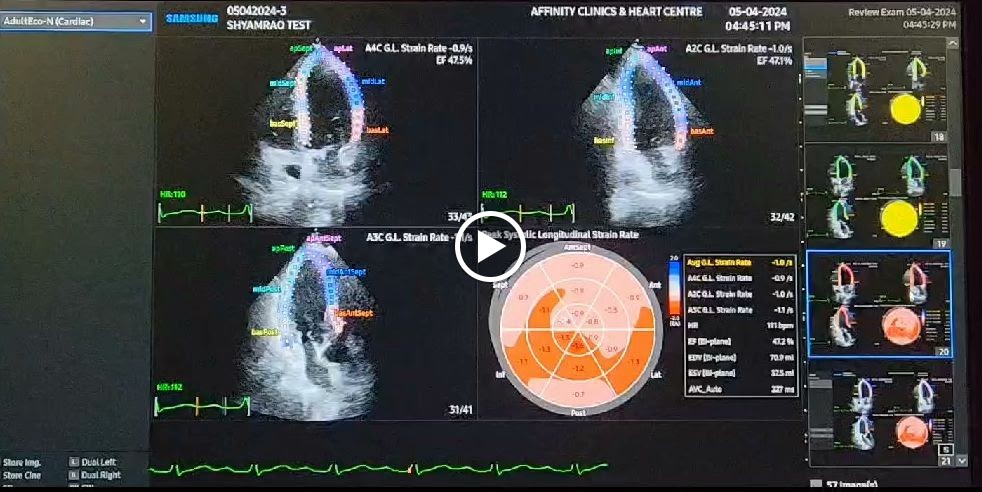

Beyond treating you with care we believe in long-term wellness. We deliver complete cardiac care *ECG *2d Echo & Colour doppler *Holter *Cardiac labs *Consultations with unmatched precision to detail and continuity of care. Trusted care for Hypertension, Diabetes, & General medicine. Guided by experience and attention to detail. Our commitment extends beyond diagnostics -- we walk with you until the problem is understood and addressed. Thoughtfully curated with clarity, consistency, and clinical depth. Pioneering heart wellness | Designed for life.